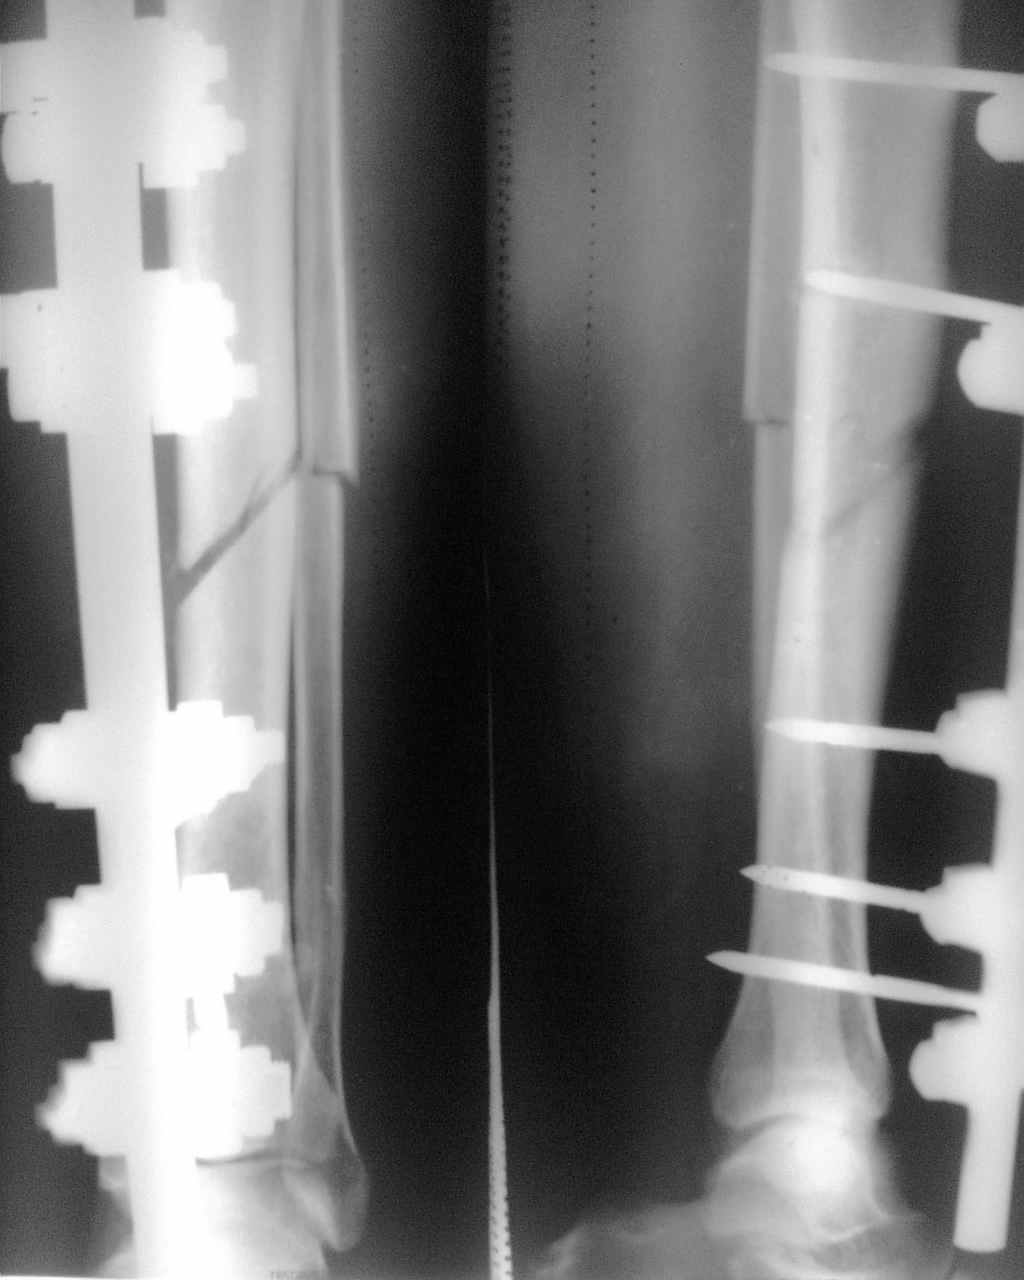

Здравствуйте коллеги! Больной 35 лет получил травму инструментом ╚ болгарка ╩ 6 недель

назад,часть кости выпилена, имеется контакт по задней поверхности б.берцовой кости,

произведена ПХО, МОС АВФ, рана зажила, АВФ демонтирован 10 дней назад, признаков воспаления

не отмечается. Планируется БИОС с резекцией м.берцовой кости Возникли вопросы: каков

уровень резекции в данном случае предпочтительней? как заполнить дефект?